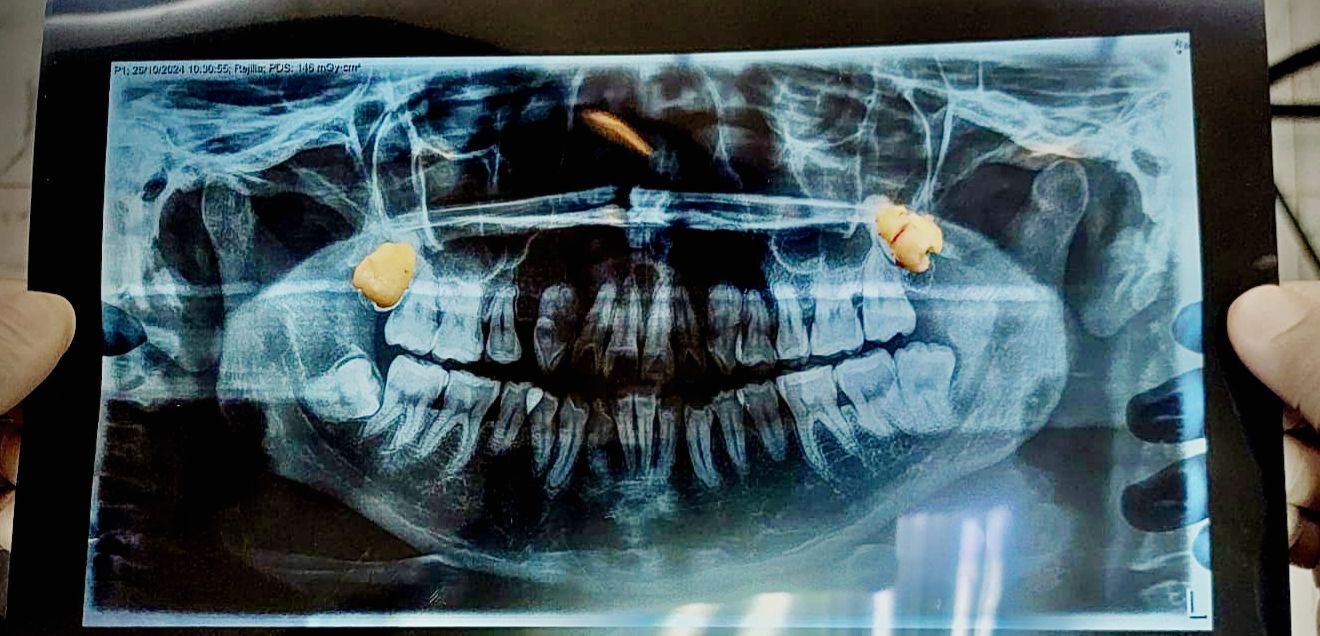

Tooth extraction is a dental procedure that involves the removal of a tooth from its socket in the maxillary or mandibular bone. Although it is preferred to keep the teeth whenever possible, in some cases it is necessary to extract them in order to maintain oral health and avoid major complications.

• Impacted or impacted teeth